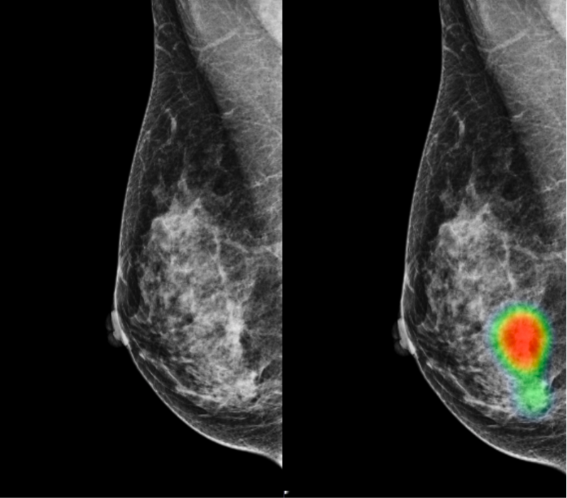

Fact Sheet Molecular Imaging And Breast Cancer Snmmi from s3.amazonaws.com With cancer cells, they appear as bright spots due to its higher metabolic rate compared to normal cells. The aim of this study is to detect the diagnostic value of pet/ct in breast cancer patients; Mammography is currently the preferred examination for breast cancer screening; Do ct scans detect breast cancer? A ct scan is one of the most frequently utilized exams to detect cancer and to show things such as a tumor's shape and size. So far, researchers at the university have. The benefits of having a ct scan usually outweigh the risks. However, your doctor may call this a pet scan.